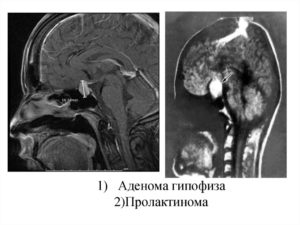

Мрт гипофиза при повышенном пролактине

МРТ гипофиза при повышенном пролактине назначается для установления наличия/отсутствия опухоли. Повышение этого гормона приводит к аденоме гипофиза. Обнаружить ее возможно только при магнитно-резонансной томографии.

Мрт гипофиза при повышенном пролактине представляет собой эффективный метод визуализации опухолевого образования в железистой области головного мозга.

Мрт гипофиза при повышенном пролактине определяет не только место локализации аденомы, но и точные ее размеры и контуры, степень врастания в смежные волокна, уровень операбельности больного. Аппаратное обследование не выявляет химического воздействия пролактина, а выявляет первопричину нарушения.

Пролактинома имеет место в классификации доброкачественных аденом. В 30 процентах случаев обнаружения опухоли гипофиза, врачи имеют дело именно с этим заболеванием. Злокачественным данный вид опухолей становится редко.

- Секретирующая пролактин микроаденома. Она считается интраселлярной, т.к. расположена в интраселлярной области в пределах турецкого седла. В диаметре опухоль не превышает 1 см.

- Секретирующая пролактин макроаденома. Диаметр данного вида пролактиномы больше сантиметра, поэтому пределами турецкого седла новообразование не ограничивается.

Опухоль гипофиза